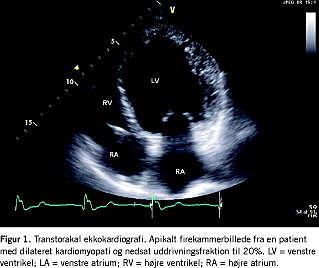

Der skelnes mellem følgende kardiomyopatier [1]: dilateret kardiomyopati (DCM): hjertemuskelsygdom karakteriseret ved dilatation og pumpefunktionsnedsættelse af venstre ventrikel eller begge ventrikler (Figur 1 ). DCM kan være slutstadiet af forskellige årsager til myokardieskade på basis af inflammatoriske, toksiske, metaboliske og infiltrative tilstande. Tilstanden er hyppigst idiopatisk, men kan forekomme familiært. Den nedsatte venstre ventrikel-funktion resulterer typisk i funktionsdyspnø. Prævalensen i Danmark er 1: 2.500 [2]. Hypertrofisk kardiomyopati (HCM): hjertemuskelsygdom karakteriseret ved øget vægfortykkelse af venstre og/eller højre ventrikel (Figur 2 ). En væsentlig følge af hypertrofien er nedsat diastolisk funktion. Hos symptomatiske patienter er brystsmerter og funktionsdyspnø næsten altid til stede. HCM kan manifestere sig klinisk som ventrikulære takyarytmier muligvis på grund af en abnorm orientering af ventriklernes myofibriller og interstitiel fibrose eller som hjertesvigt på grund af nedsat diastolisk funktion. Der ses familiær forekomst, og der er fundet flere genmutationer, der er associeret med HCM. Prævalensen i Danmark er 1:500. Arytmogen højre ventrikel-kardiomyopati (ARVC): hjertemuskelsygdom, der er karakteriseret ved fedtinfiltration og fibrose i myokardiet og primært inddrager højre ventrikel. ARVC forekommer bl.a. familiært og manifesterer sig klinisk med ventrikulære arytmier, der udgår fra højre ventrikel og således typisk har venstresidig grenblokskonfiguration. Kardinalsymptomet er palpitationer, (nær)synkoper og pludselig død. Der er fundet flere genmutationer, der er associeret med sygdommen. Prævalensen i Danmark er 1:5.000.